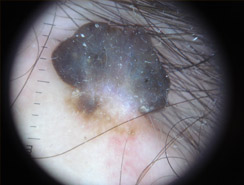

Dermatoscopia

Lo studio e la diagnosi delle neoformazioni cutanee attraverso strumenti specifici indicati per un'analisi delle caratteristiche strutturali superficiali e profonde delle varie neoformazioni cutanee: dermatoscopia, dermalite a luci fotocromatiche, mappatura nevica con videodermatoscopia digitale.

Al fine di una corretta diagnosi dei nevi, e dunque di un'efficace prevenzione da forme tumorali, è indispensabile visionare in profondità i caratteri di ogni formazione nevica. Ciò è reso possibile dall'utilizzo del dermatoscopio e dalla concomitante mappatura nevica, con l' eventuale rimozione chirurgica o laser di: